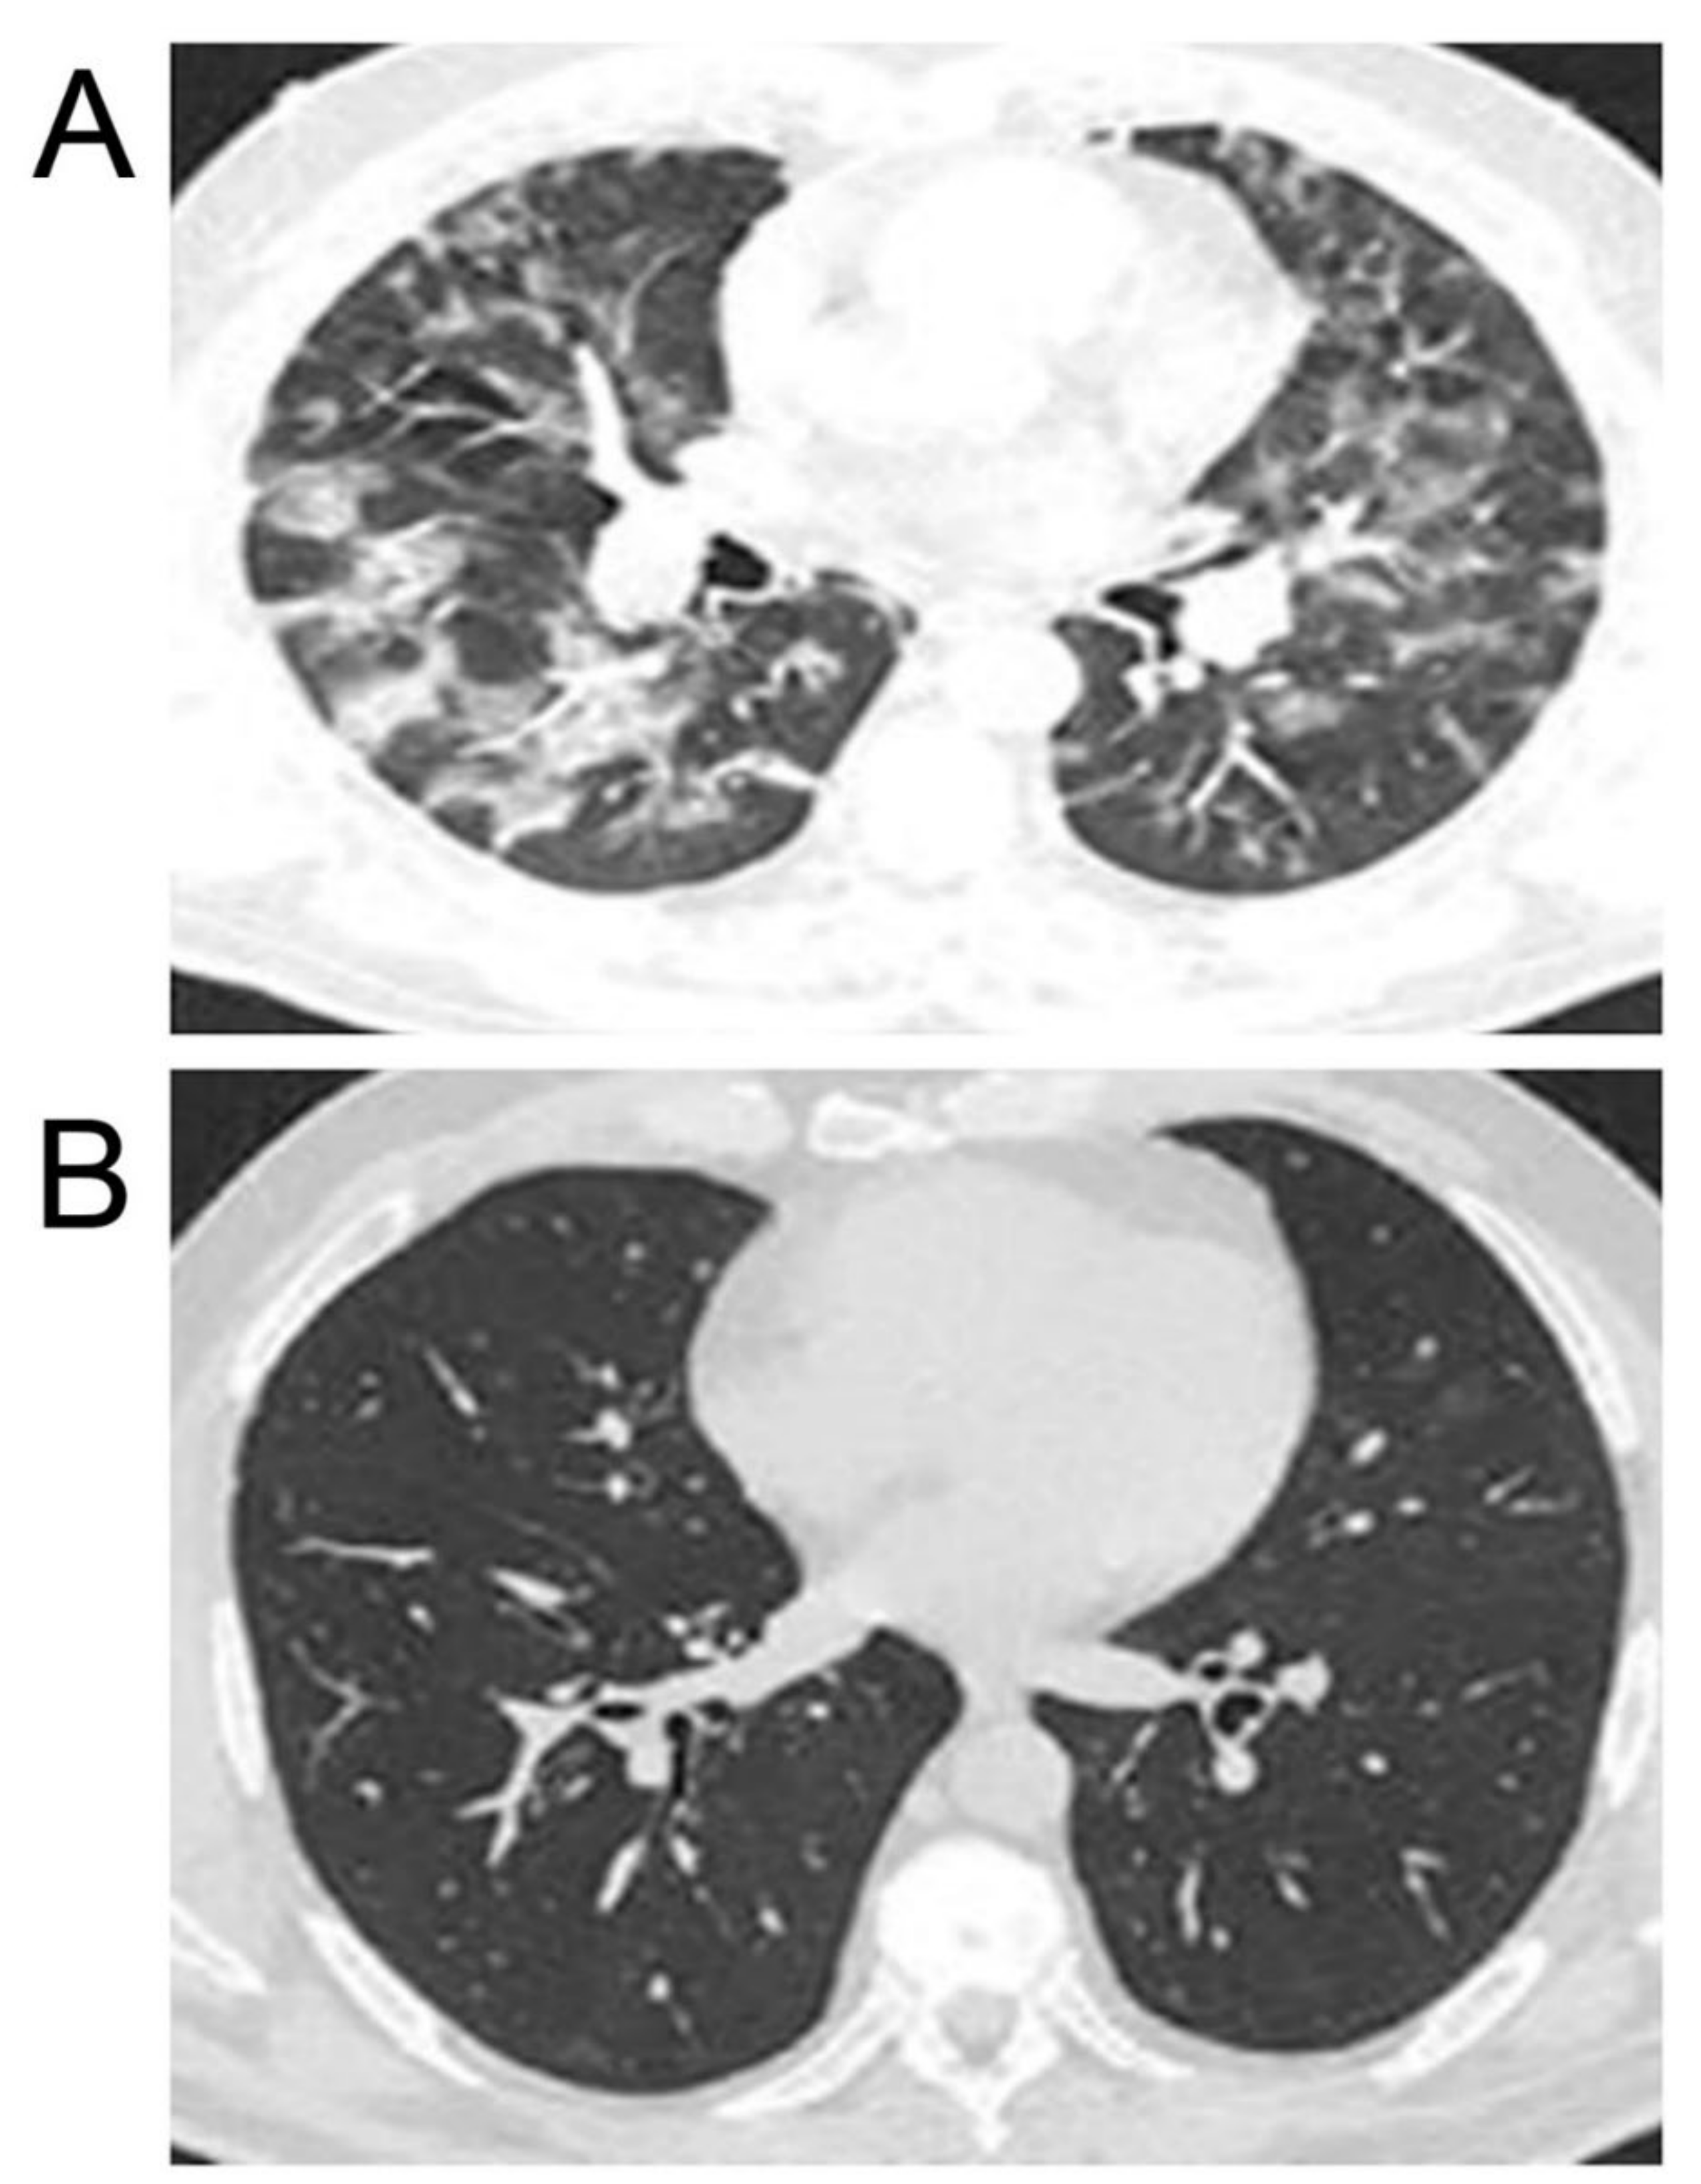

The combination of hot helium–oxygen breathing mixtures with inhalations of STS in patients with clinically severe cases with high initial lung damage, 70–85% (8 patients), resulted in full computer tomography (CT) remission of coronavirus pneumonia 45–65 days after treatment starts without respiratory failure and signs of pneumofibrosis (Figure 7). In the control group of patients (18 patients) with similar initial indices in 3 and 6 months after standard treatment, CT signs of pulmonary fibrosis (degree of lesion 45–50%) and lowered functions of external respiration (FER) (35–40%) were revealed in 12 and 8 from total 18 cases, respectively. Differences between the main group of patients (combined use of inhaled hot helium–oxygen mixtures and sodium thiosulfate) and the control group (conventional therapy) were highly significant (p < 0.01).

Figure 7. The results of computer tomography (CT) of the lungs of COVID-19 patients. (A) Severe case. 80% lung injury before STS treatment. (B) 5% lung injury after 2.5 months of application of hot helium–oxygen mixtures and inhalation of STS.